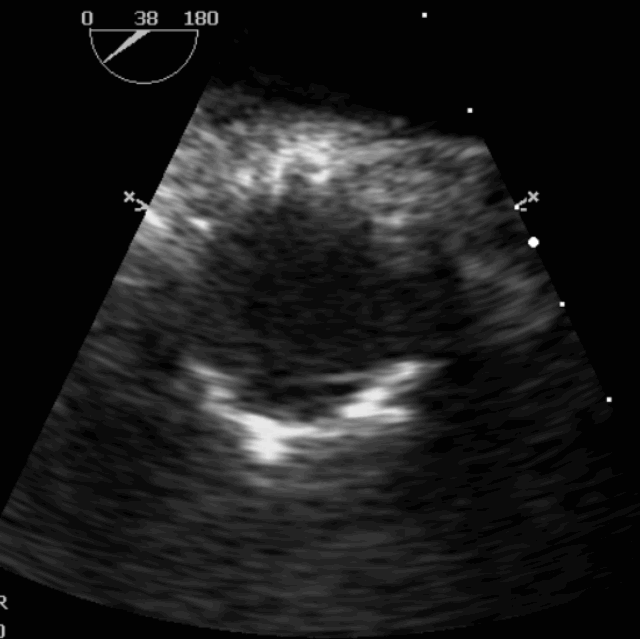

术前超声影像图

术后超声影像图